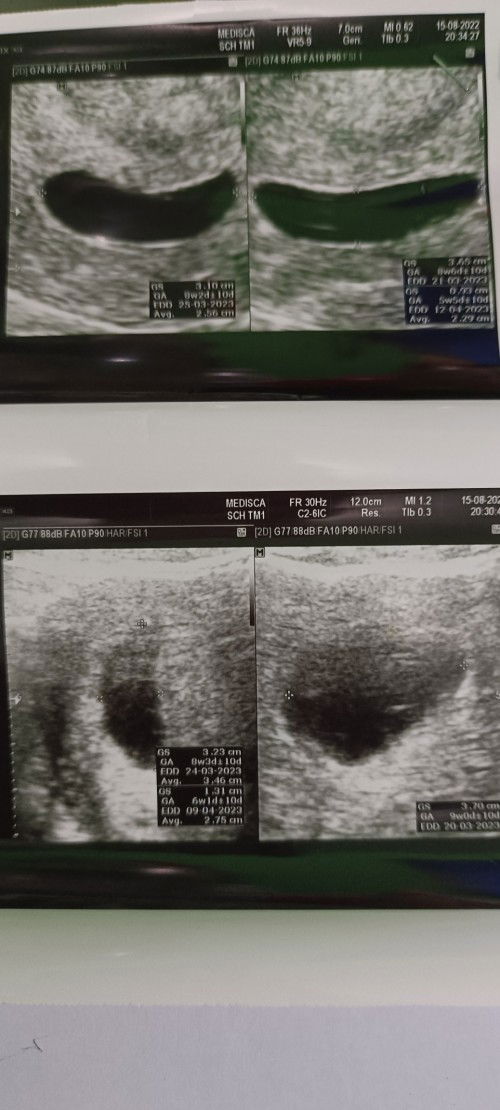

Bunda2 ada yg punya pengalaman hamil BO? Saya sudah 3 minggu terakhir keluar flek kecoklatan (tidak setiap hari, hanya ketika kecapean), konsumsi penguat selama 2 minggu. Malam ini keluar flek dan gumpalan darah sebesar biji cabai langsung USG, lewat perut dan vagina tetap tidak ada janin. Dokter bilang hamil BO karena ukuran kantung sudah besar tapi janin tidak ada dan harus segera di kuret. Sedih, kecewa dan takut. Tapi jika memang harus di kuret, mungkin memang bukan rezeki kami. Apakah bunda2 ada yg punya pengalaman serupa? #bantusharing